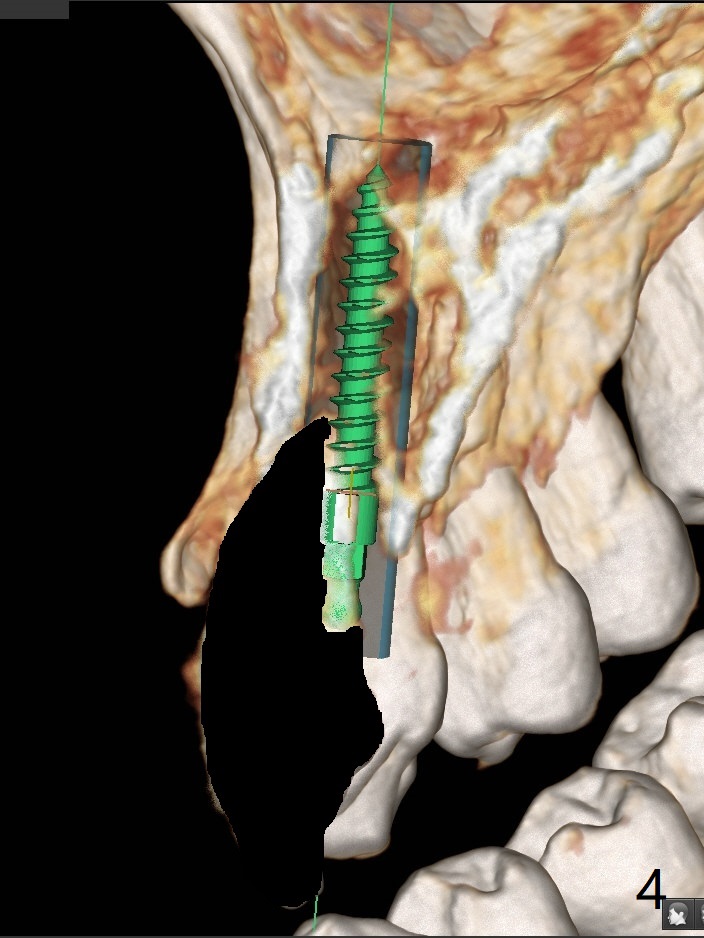

A 58-year-old man recently had sudden pain at #7 with labial plate loss (Fig.1 CT taken 3 years earlier). To avoid the labial placement of the large implants at #8, and 9, the implant at #7 will be smaller and palatally inserted (Fig.2). Fig.3 is a coronal section of 3D image of #7, showing the labial (B) and palatal (P) crests. After extraction (Fig.4 black), the narrow implant is placed between the crests (green). To repair the coronal labial plate, a piece of PRF membrane (Fig.5 blue) is placed inside the socket, followed by sticky bone (red circles). The portion of PRF membrane outside the socket will be flipped palatal, inserted into the abutment with a pre-punched hole and finally tucked underneath the palatal gingiva.